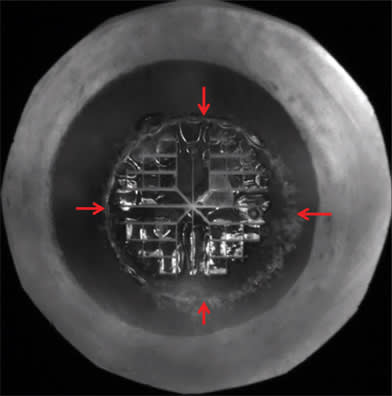

For the capsulorhexis, the OCT detects the iris boundaries so the laser can be safely directed inside the iris even if it is not dilated symmetrically (Figure 3). Research has shown that the capsular edge tensile strength is equal to that of manual techniques (Figure 4). The laser incision formed with cavitation bubbles may have improved strength and resistance to manual trauma during phaco and lens implantation, which could reduce capsular extensions. Symmetrical uniform fibrosis and healing may also be important for accommodating IOLs that rely on symmetrical contractile forces to translate into axial movement.

Figure 3. Perfectly sized (5.0 mm) and positioned, round anterior capsulotomy (red arrows) with four-quadrant segmentation and softening (0.5 mm cubes) created by femtosecond laser.